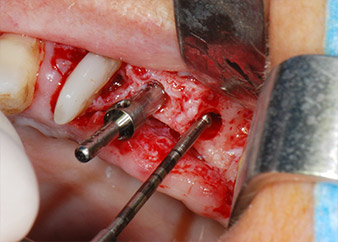

Преди поставянето на импланта, инфектираната тъкан е отстранена от алвеоларната кост в имплантното ложе и около зъба-абатмънт с накрайник, проектиран за оформяне на костта и събиране на костни блокове (Piezomed, накрайник B5) (Фиг. 6 и 7).

Имплантологичното ложе е подготвено в позиции 25 и 26 с ротиращи инструменти, използвайки обратен наконечник 20:1 с усъвършенстван и мощен имплантологичен мотор (Implantmed, W&H) (Фиг. 8).